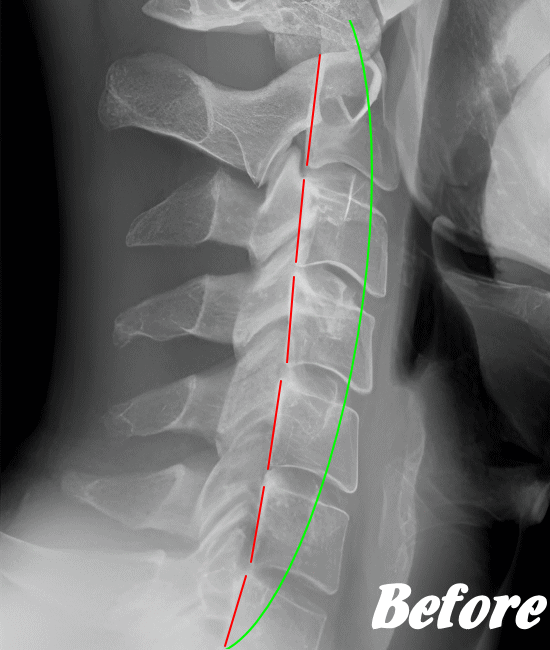

HALOカイロプラクティック☆平和島整体院では、骨盤(仙腸関節)から背骨(腰椎、胸椎、頸椎)、肋骨(肋椎関節)、肩甲骨(肩甲胸郭関節)などを調整し緩めることで、首(頚椎)にかかる負担を取り除き、可動域を良くして痛みを解消していきます。

首や肩周りの症状では、肩甲胸郭関節(肩甲骨周辺)を調整することは必須です。